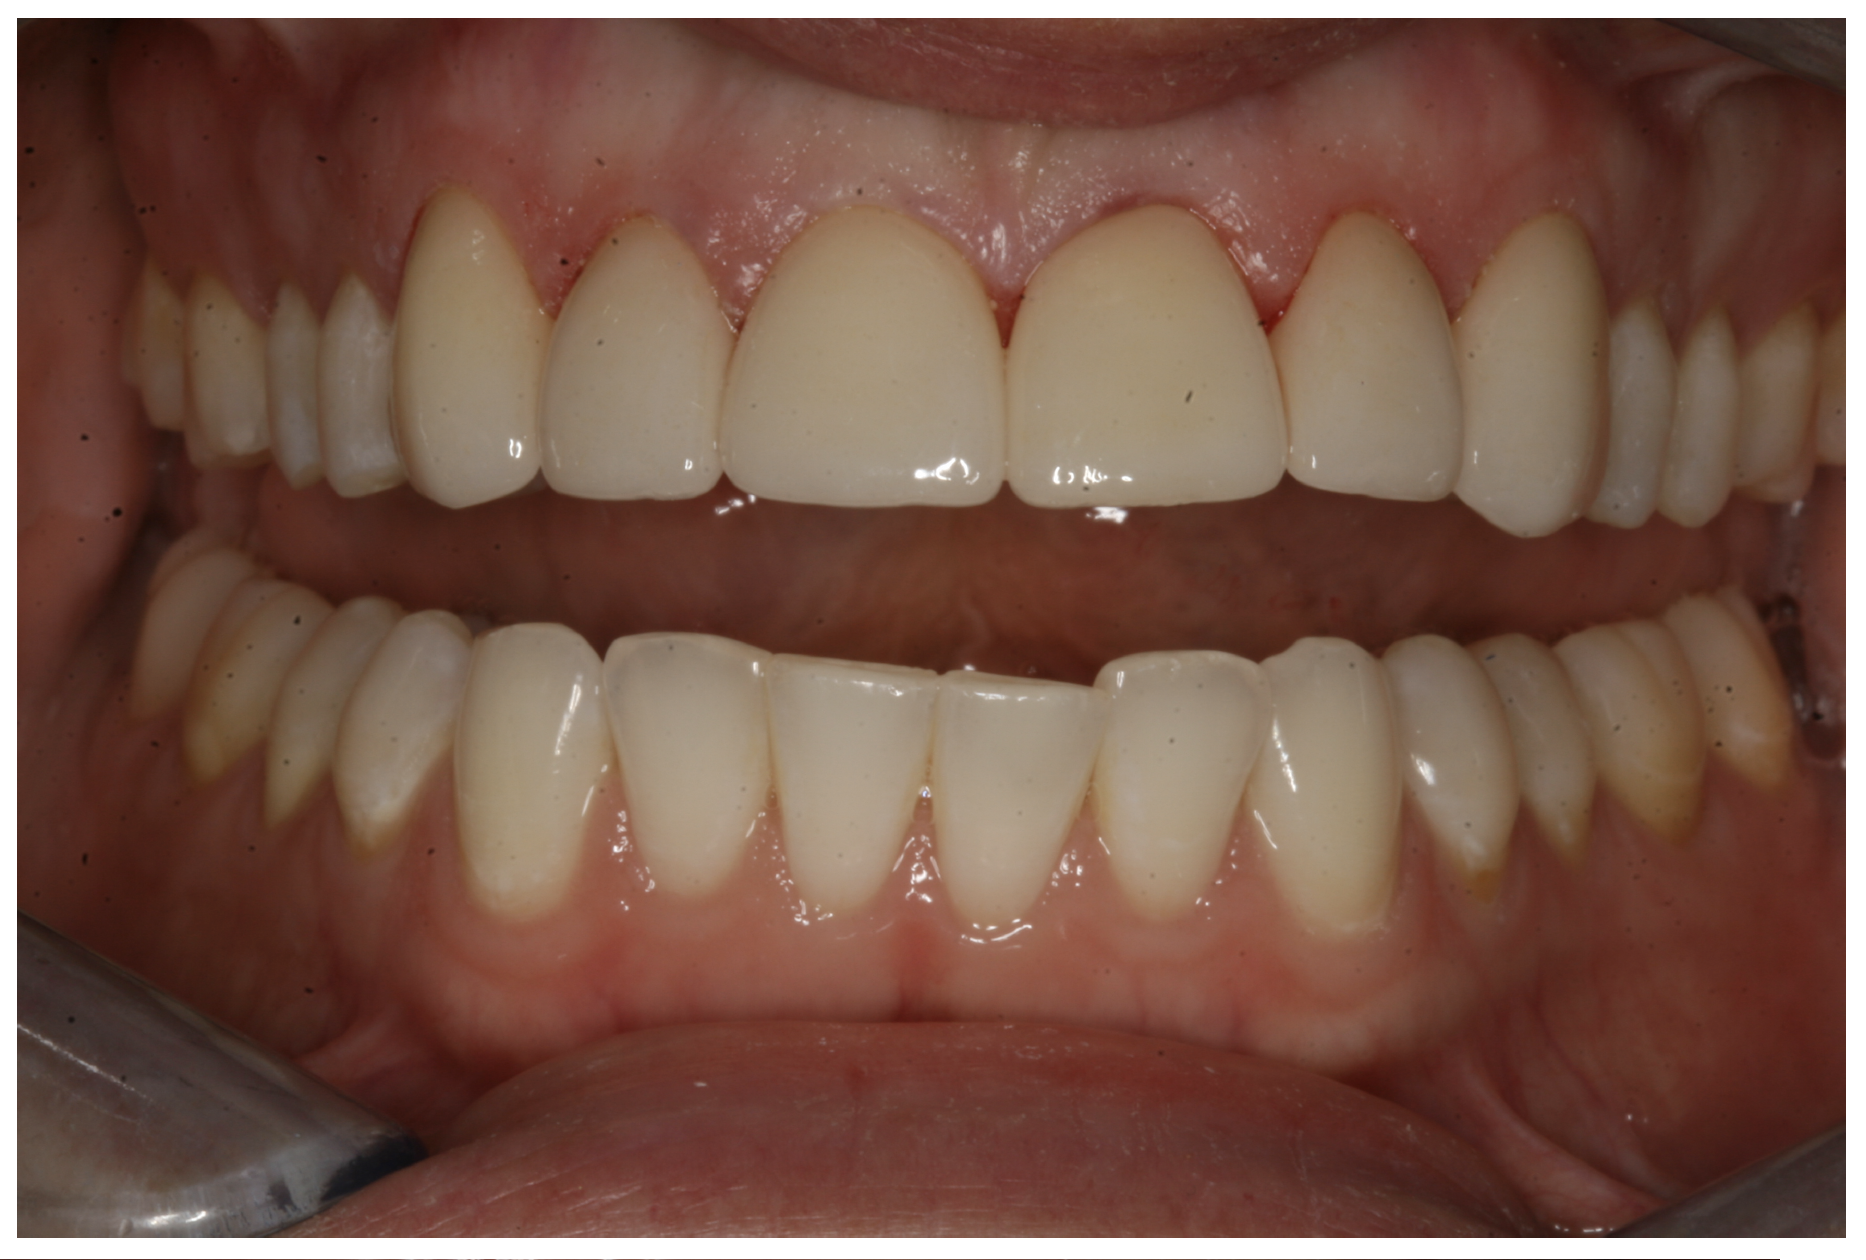

In another case, the patient presented with very thick, bulky, over-contoured veneers done on teeth Nos. 7 through 10 when she was a teenager. There also was some recession and staining at the margins (Figure 12). The clinician decided to restore teeth Nos. 6 through 11. A preparation design was required with provisionals removed. As tooth structure could not be regrown, the practitioner made the best of the situation. There was good gum health, which is important for isolation and marginal seal. The clinician cemented with a universal, doing six units at one time. Minimal cleanup was required. At a 1-month follow-up visit, although tissue still was settling in, the contours were natural. After a year (Figure 13), the gum filled in nicely and was in excellent health, and there was good color stability and seamless marginal integrity.